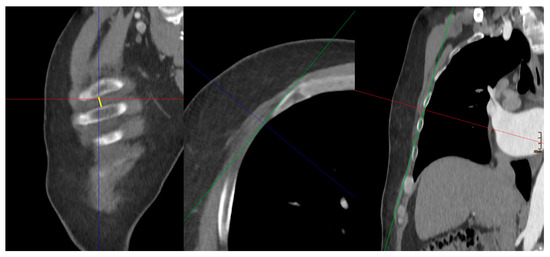

ICS–Width of the intercostal space:

In multiplanar reformatting (MPR), the width of the corresponding intercostal space just below the nipple reflecting the entry site was measured.

Figure 3. ICS–Width of the intercostal space: yellow. The red, green, and blue lines represent the orthogonal planes generated by the Multi-Planar Re-construction (MPR) plugin, facilitating three-dimensional assessment of the CT dataset.